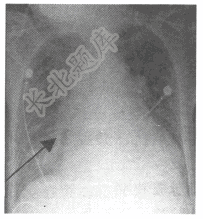

- 单项选择题男性患者,70岁。因呼吸困难、咳出泡沫样痰入院。胸部X线平片如下图。右中肺野斜行线状影(箭头)为

A、Kerley C线

B、盘状肺不张

C、Kerley A线

D、胸腔积液

E、Kerley B线